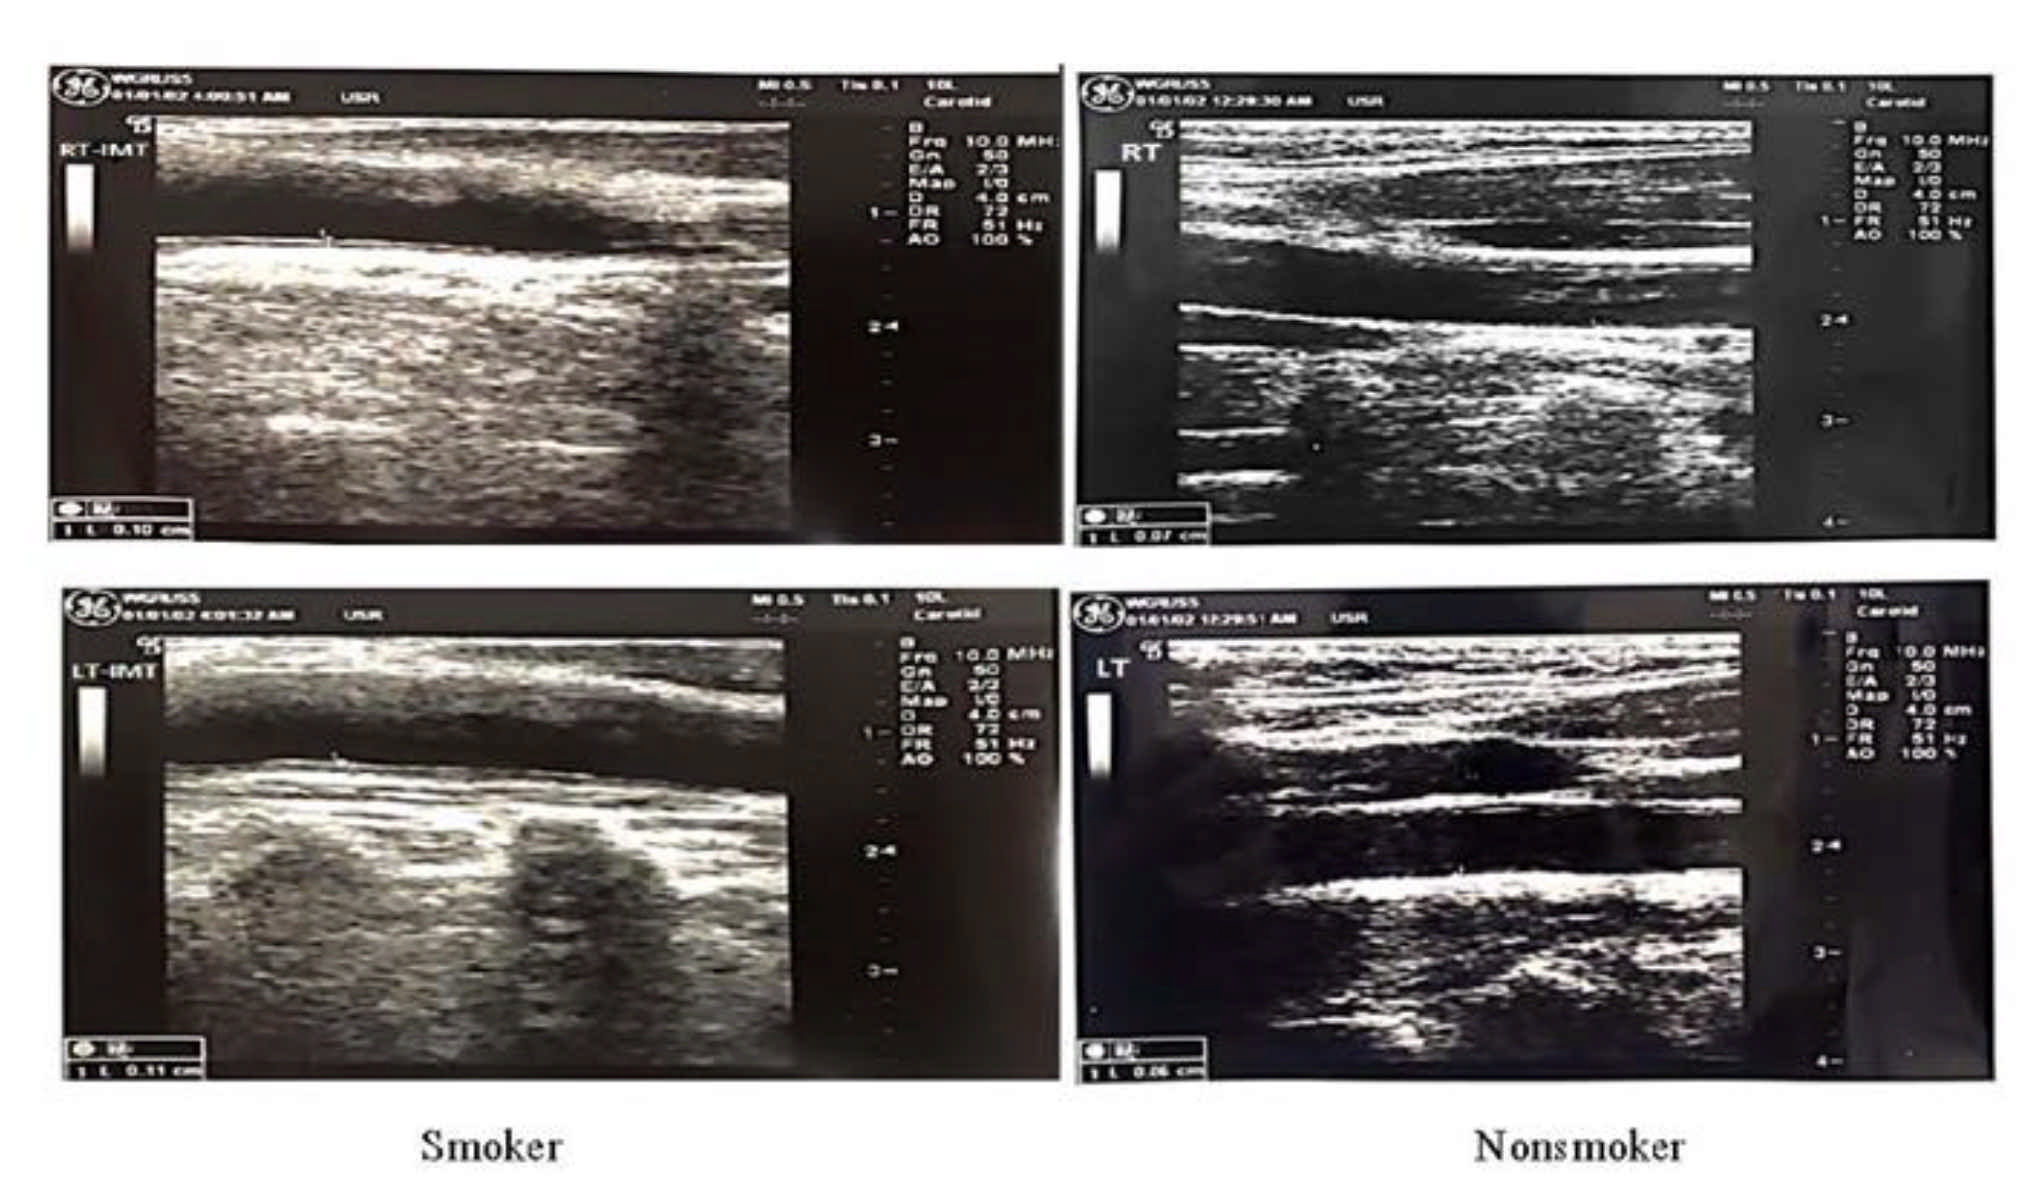

2.5. Intima–Media Thickness (IMT) Measurement of the Common Carotid Arteries

3.2. Smoking with RCA and LCA IMT

| RCA (mm) | 0.58 ± 0.22 | 0.72 ± 0.14 | 0.005 |

| LCA (mm) | 0.62 ± 0.13 | 0.70 ± 0.14 | 0.04 |